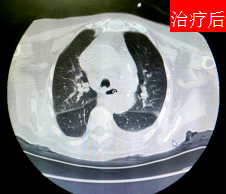

(治疗前后胸部CT对比)